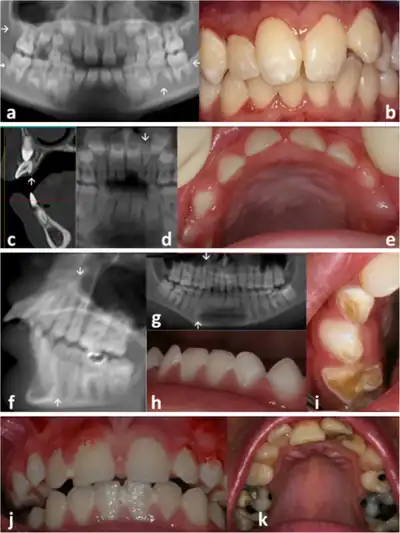

| Face | Wizened faceies. Sunken eyes, large ears, thin pointy nose. Small chin. Dental caries, enamel hypoplasia | |

| Skin, hair, nails | Photosensitivity. Wrinkled and aged appearing skin. Thin dry hair, prematurely gray hair. Poor venous access. | |

| Vision | Corneal opacification.

Cataracts [36–86%]. Usually bilateral, most develop by 4 years of age. Pigmentary retinopathy (“salt and pepper”)[43–89%]. Miotic pupils, Optic disk pallor, Enophthalmos, Narrow palpebral fissures. |